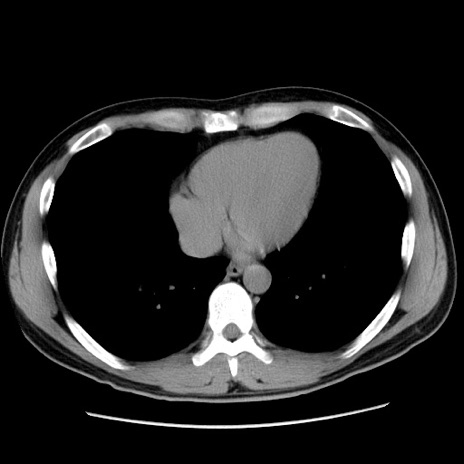

冠状断像